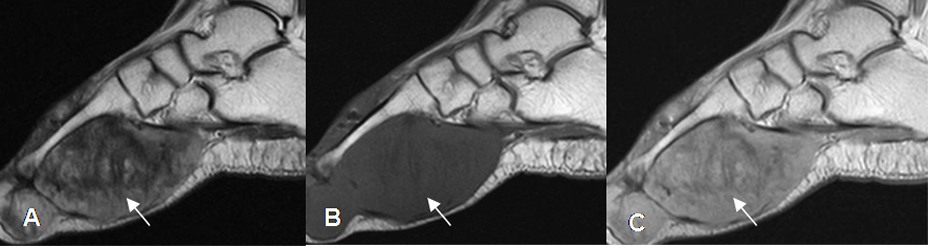

Fig 113. Enfermedad de Dupuytren.

A: RM sagital en T1, B: RM sagital en T2 y C: RM sagital en STIR. Deformidad en flexión del dedo, con imagen ovalada que se relaciona con el mecanismo flexor. Esta lesión es hipointensa en T1 y T2 e hiperintensa en STIR, por el componente fibroso y corresponde a enfermedad de Dupuytren.